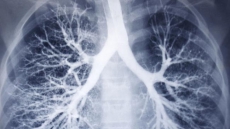

How Fast Are Your Lungs Ageing? Here's The Lowdown

Mothers who smoke, respiratory infections and the date you were born all contribute to determine how fast your lungs are ageing